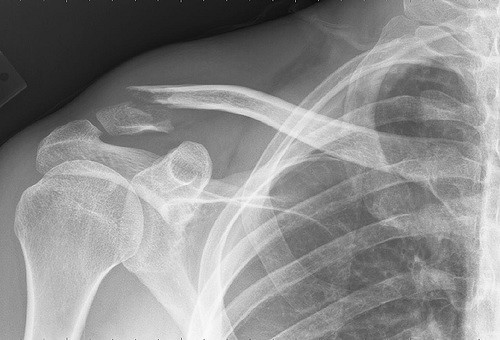

Riding is a great way to break a collar bone. (1) So don’t be a fool; get the insurance.

Common sense really. It seems like an easy way to do the trip on a budget: save yourself a hundred bucks by not getting travel health insurance. This is possibly the biggest mistake you’ll ever make. Not only is there the chance that the nearest hospital won’t even treat you, there is a 100% chance that they won’t do it for free, and trust me, without government subsidies, medical bills rack up real fast. So don’t be a fool; get the insurance. Just make sure it will cover you if you injure yourself while riding.

(1) Image by J Bizzie /CC SA 03